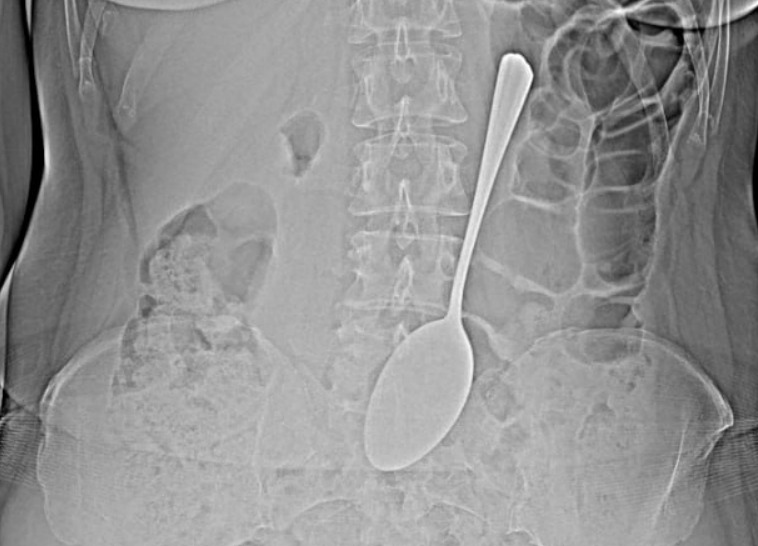

Жительница Бурятии проглотила ложку длиной 18 см

Врачи БСМП в Улан-Удэ спасли женщину, которая проглотила столовую ложку длиной 18 см.

Ложку эндоскописты достали из желудка с помощью эндоскопа и соответствующих инструментов, что помогло избежать сложной хирургической операции.

«Инородные предметы в желудке могут спровоцировать перфорацию желудка, кишечную непроходимость. Если мелкие предметы вроде монет могут выйти из организма самостоятельно, то в случае со столовой ложкой все могло быть серьёзнее», - прокомментировал врач-эндоскопист БСМП имени Ангапова Валентина Бабудоржиева.

После проведённой процедуры женщину отпустили. Каким образом она сумела проглотить ложку, она так и не рассказала.